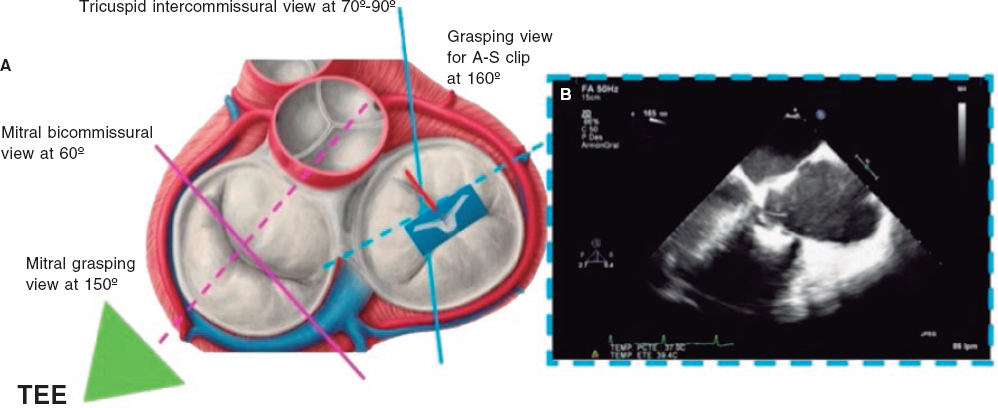

There are 4 key TEE views to guide the TV clip implantation: 4-chamber, bicommissural, transgastic, and grasping views (capture of tricuspid leaflets inside the device). The former views have already been described; we will now focus on the latter.

Grasping view

This is the view that better shows the leaflets that should be treated and the clip with wide open arms. Finding the best grasping view for clip implantation in the tricuspid position is one of the most complex and important steps during the procedure. The first limitation to find it is that, unlike what happens in the mitral valve, there are no clear anatomical references to guarantee the perpendicularity of the clip with respect to the leaflets. That is why a correct alignment at transgastric level is critical. After finding this alignment, the transducer is removed to look for the grasping view at mid-esophageal level.

The most common strategy is to place a clip between the A and S leaflets and towards the TV most central region. To acquire the grasping view and see the A and S leaflets we should start at the intercommissural view and the multiplanar view, and the grasping view will often be found at around 160° (figure 4). Another option is to perform a TEE transducer sweep from 0° to 180° until finding a direct grasping view to actually see the leaflets and the clip with wide open arms. In any case, every patient should be handled individually since the TV has more anatomical variations than the mitral valve. Also, the angle between the intercommissural view and the coaptation line of the A and S leaflets can be < 90º and mislead the multiplanar assumptions. The real-time 3D TEE can be useful to guide the clip, but not so much with mitral procedures.

Figure 4. Search for the grasping view for the clip in the anteroseptal (A-S) position with respect to the center of the tricuspid valve. A: grasping view for A-S clip (discontinuous blue line). B: transesophageal echocardiogram (TEE) at 160° showing the clip with wide open arms and the anterior and septal leaflets resting on them.